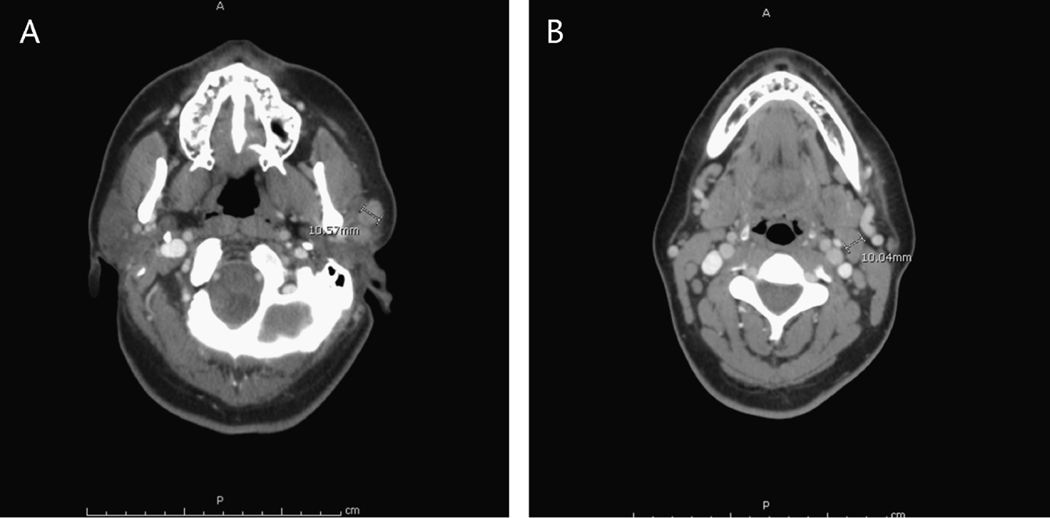

Description:We report a patient who presented with unilateral periorbital edema after a short-term travel to an endemic area for Chagas disease and exposure to triatomine (reduviid) bugs. The diagnosis, however, was furuncular myiasis, not Chagas disease. This case emphasizes that there are multiple parasitic agents besides | that may be associated with clinical findings consistent with Romaña sign.